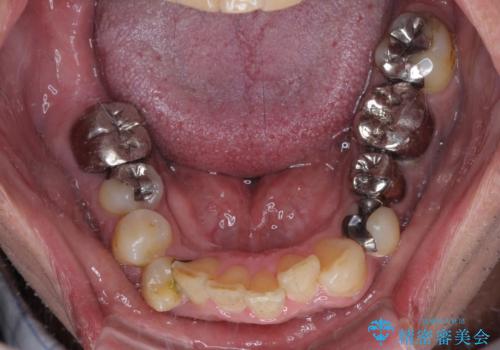

- 黄ばんだ前歯や目立つ奥歯の銀歯をきれいにしたいとのことで来院された患者様です。

欠損している歯や、割れてしまって抜歯の必要な歯などがあり、咬合力が強いため欠損部はインプラント補綴を前提に治療を行うこととしました。

しかしながら、左下の抜歯部位は骨欠損が著しく大きく、多大な垂直的骨造成を要するため、3歯を支台としたブリッジによる補綴治療とし、右下のみをインプラント補綴としました。

小さい修復物の銀歯が装着されている歯はセラミックインレーにて、その他はオールセラミッククラウンにて補綴治療を進めることとしました。